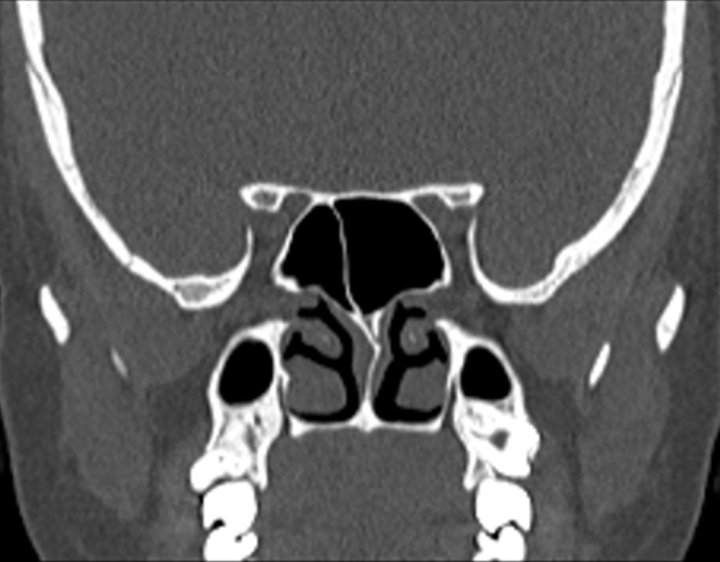

Click any image for labels.